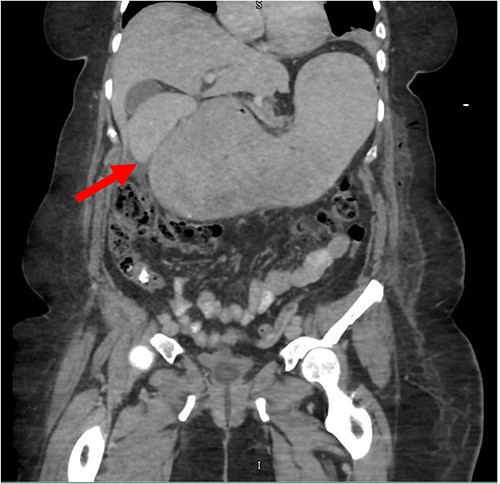

Despite the insertion of the NGT yielding 1500 cc output in 24 hours, the patient continued to experience severe abdominal pain. Urgent abdominal and pelvic computed tomography (CT) scans were taken, as seen in Figs 2–4. The CT scans showed gastric distension and the spleen positioned anteriorly in the right upper quadrant. Consequently, the decision was made to promptly bring the patient to the operating room for a diagnostic laparoscopy with plan to detorse the spleen.

CT of the abdomen and pelvis (axial slice) showing gastric distention and the spleen positioned anteriorly in the right upper quadrant.